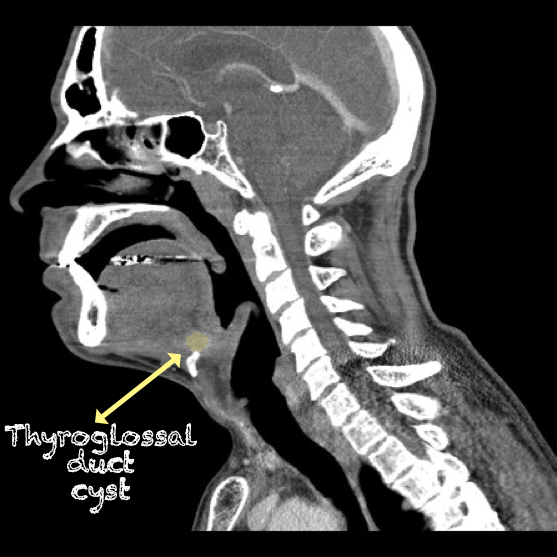

- Thyroglossal Duct Cyst with ring enhancement on CT:

- Figure 36 and 37. Thyroglossal Duct Cyst on CT

Thyroglossal duct cyst26

- Thyroglossal duct cysts typically related to hyoid bone:

- Often midline

- 25%-suprahyoid-submental region

- 75%-Infrahyoid or at the level of hyoid

- Variable sonographic appearance:

- Well-circumscribed anechoic cyst

- Increased through transmission

- Hypoechoic with internal debris

- No internal vascularity

- Heterogeneous pattern seen in repeated infections and hemorrhage due to prior aspirations

- Pseudo-solid echogenic appearance from proteinaceous contents secreted by epithelial lining

- Figure 34 and 35. Thyroglossal Duct Cyst